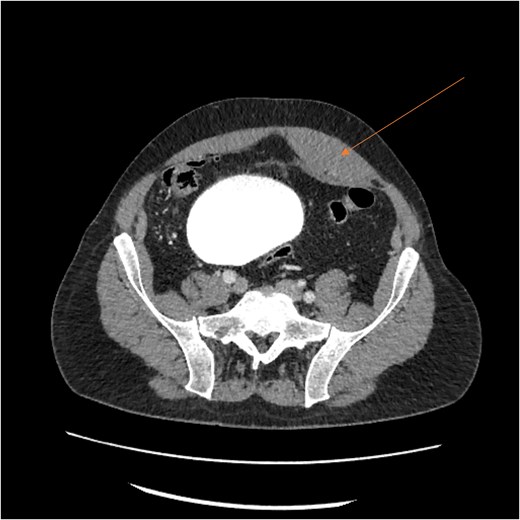

A massive transfusion protocol was initiated, and the patient received four units of packed red blood cells, six units of fresh frozen plasma, two units of platelets, and bicarbonate boluses. A CT abdomen and pelvis was performed to reassess the RSH, revealing an interval enlargement (15.3 × 10.7 × 20.4 cm) with a focal blush at the inferior portion, concerning for active extravasation (Fig. 3). The patient was hemodynamically stabilized and underwent inferior vena cava (IVC) filter placement once his hemoglobin reached 8 g/dl.